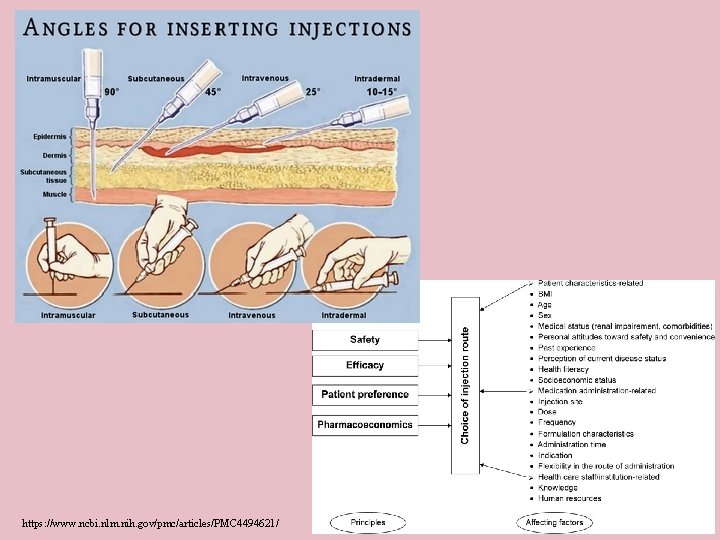

https: //www. ncbi. nlm. nih. gov/pmc/articles/PMC 4494621/